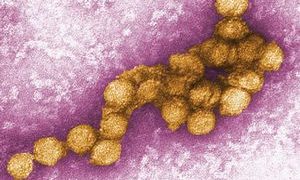

ウシ(牛)の病気  ウイルス

ウイルス  ウイルス

ウイルス  ウイルス